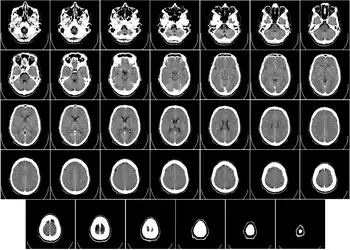

Imagen estructural y funcional

Hay varios métodos para detectar los cambios de actividad cerebral mediante imágenes tridimensionales de los cambios locales en el flujo sanguíneo cerebral. Los antiguos métodos son la SPECT y la PET, que dependen de la inyección de marcadores radiactivos en el torrente sanguíneo.

La imagen por resonancia magnética funcional (IRMf), tiene considerablemente mejor resolución espacial y no implica ninguna radiactividad.[25] La IRMf puede localizar los cambios de actividad cerebral en regiones tan pequeñas como 1 mm³ (milímetro cúbico).

El inconveniente es que la resolución temporal es pobre: cuando aumenta la actividad cerebral, el flujo sanguíneo responde con un retraso de 1 a 5 s (segundos) y tiene una duración de al menos 10 s. Por lo tanto, la IRMf es una herramienta muy útil para saber cuales regiones del cerebro están involucradas en una determinada conducta, pero da poca información sobre la dinámica temporal de sus respuestas. Una ventaja importante de la IRMf es que, debido a que no es invasiva, puede ser fácilmente utilizada en seres humanos.